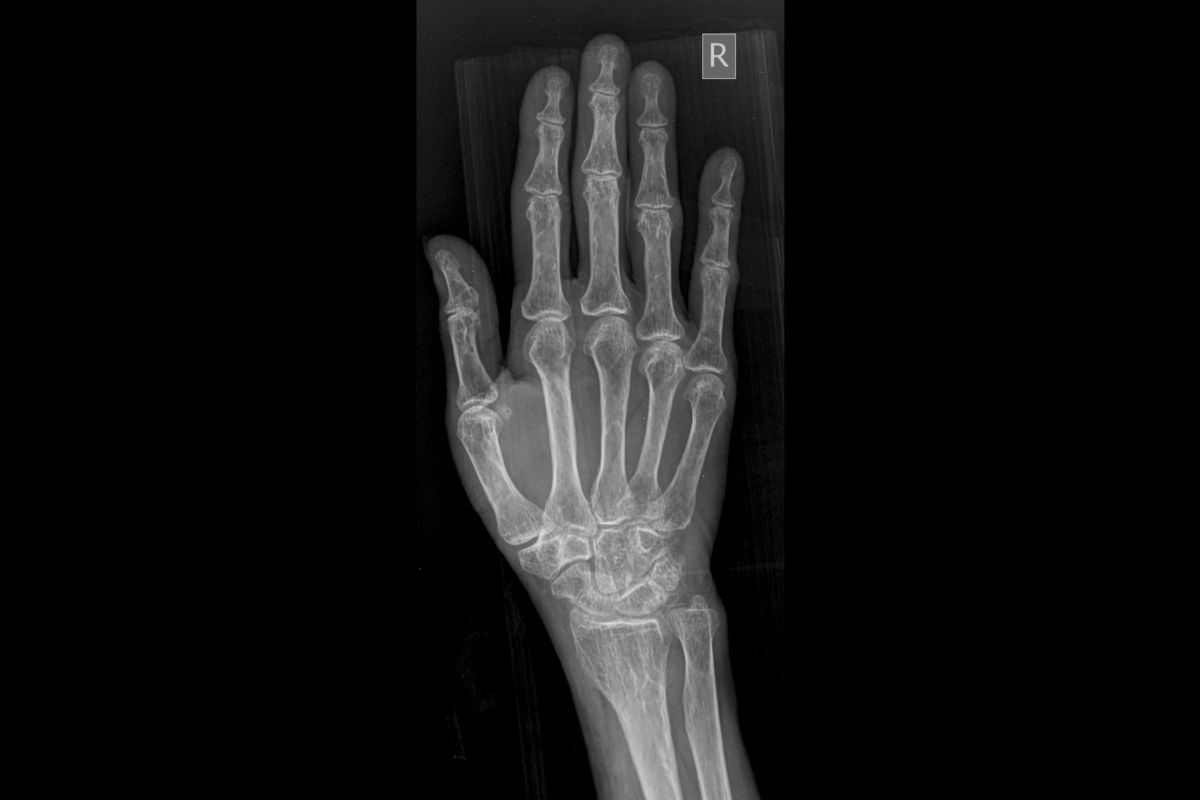

Why the Hand & Wrist Require a Specialist

The hand and wrist together contain 27 bones, more than 20 joints, dozens of tendons and ligaments, and several major nerves — all packed into a remarkably small space. This complexity makes the hand and wrist one of the most technically demanding areas to treat with regenerative medicine.

Most clinics offering stem cell therapy focus on large joints like knees and hips. At Stem Cell Carolina, the treating physician is specifically trained in interventional musculoskeletal medicine and regularly treats small joint conditions — including thumb base arthritis, TFCC tears, carpal tunnel, De Quervain’s tenosynovitis, and trigger finger — under real-time ultrasound guidance.

This means every injection is placed with precision into the exact structure causing pain — not estimated by surface landmarks. For hand and wrist conditions, where a few millimetres of accuracy can make the difference between effective treatment and a missed target, this matters enormously.